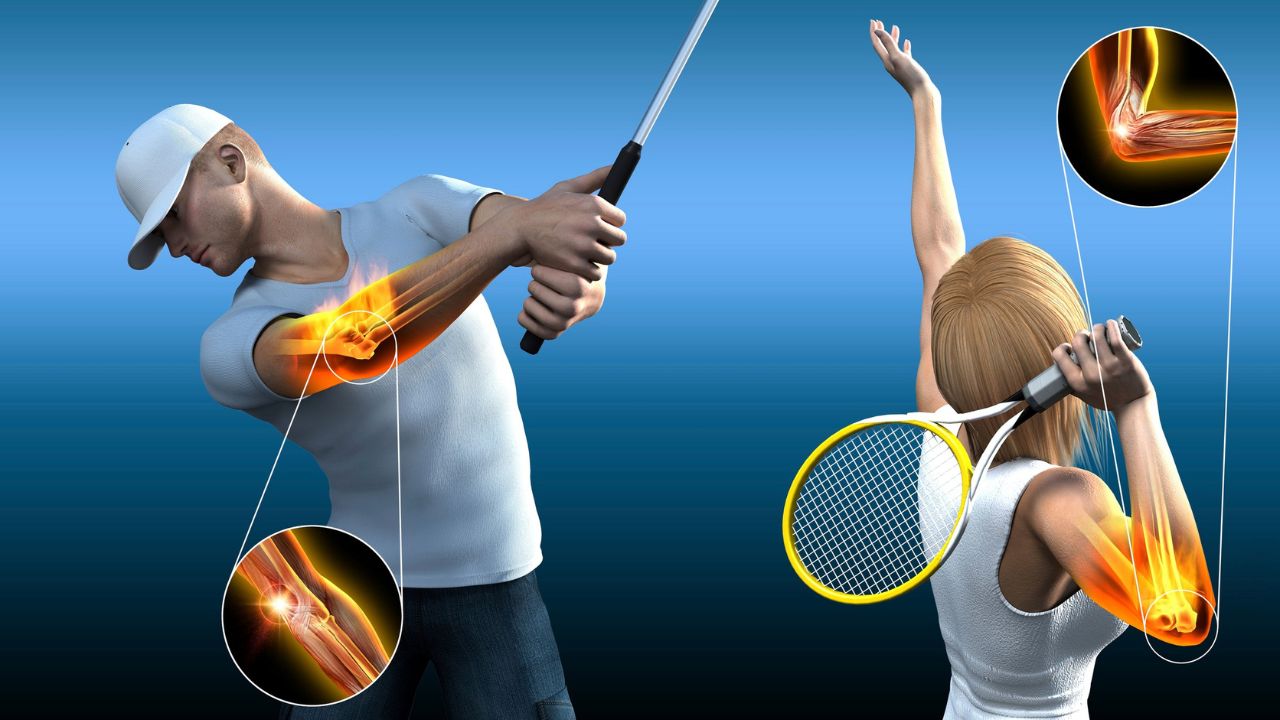

Epicondilite Lateral Agendar consulta A Epicondilite Lateral, popularmente chamada de “Cotovelo de Tenista”, é uma causa muito comum de dor na parte externa do cotovelo.